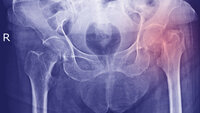

Hoftebrudd: Høyere dødelighet ved tidlig utskriving

Det antyder en ny norsk studie.